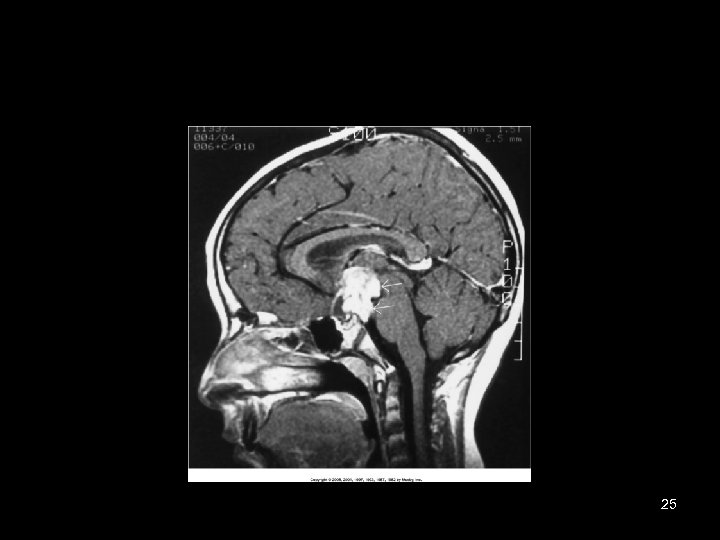

25